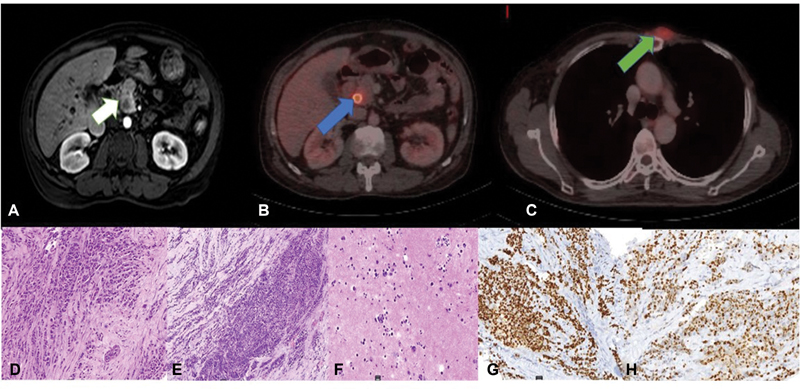

A 51-year-old man was diagnosed with left-sided breast cancer. He underwent a radical mastectomy, which on histopathology showed ILC and two positive axillary lymph nodes ([Supplementary Fig. S1A], available online only); estrogen receptor/progesterone receptor (ER/PR) was positive (Allred score—7/8 and 5/8, respectively) and HER 2 was negative ([Supplementary Fig. S1B–E], available online only). He received standard anthracycline and paclitaxel-based adjuvant chemotherapy. He also received locoregional radiation to chest wall and supraclavicular fossa. Patient was on maintenance tamoxifen when he presented with jaundice and anorexia after a disease-free interval of 2 years. On clinical examination, he had icterus and a 2 × 2 cm fixed chest wall lesion at the second costochondral junction. Biochemistry investigations revealed conjugated hyperbilirubinemia (total bilirubin—28 mg/dL, conjugated bilirubin—11mg/dL, serum glutamic-oxaloacetic transaminase—256IU/L, serum glutamic-pyruvate transaminase—109IU/L, alkaline phosphatase—249mU/mL) suggestive of obstructive jaundice. Serum CA-19.9 was within normal limits (24.35 U/mL). Abdominal ultrasound showed central intrahepatic biliary tract dilatation with a dilatated common bile duct (CBD) of 13 mm with an abrupt cutoff at the lower end. Magnetic resonance cholangiopancreatography was suggestive of a lesion in the head of pancreas measuring 9 × 8 mm involving the intrapancreatic CBD with upstream dilatation of suprapancreatic CBD, common hepatic duct, and intrahepatic biliary tract ([Fig. 1A]). A staging positron emission tomography-contrast-enhanced computed tomography showed increased uptake in an ill-defined soft tissue mass involving intrapancreatic bile duct and adjacent pancreatic parenchyma ([Fig. 1B]) (SUVmax—7.77) and a left parasternal soft tissue mass (SUVmax—5.88) ([Fig. 1C]). There was no other uptake on positron emission tomography in any other organ. A self-expandable metallic biliary stent was placed for recurrent cholangitis. Biopsy of chest wall lesion was recurrent ILC ([Fig. 1D]) and ER/PR was positive ([Fig. 1G, H]), consistent with that of the primary breast tumor. Radiological impression was that of an isolated pancreatic head mass. Two differentials of solitary pancreatic metastasis of lobular carcinoma and a second primary pancreatic head carcinoma were kept in mind. However, isolated pancreatic head metastasis from BC is extremely rare. In case of BRCA1 and BRCA2 mutation carrier incidence ratio for second pancreatic cancer reported to be 2.55 and 2.13, respectively.[7] On germline mutation analysis with hotspot common mutation testing with focused sequencing the patient had no pathogenic BRCA1 or 2 germline mutation. Staging laparoscopy was planned to be followed by a pancreaticoduodenectomy if resectable and localized pancreatic lesion along with wide excision of chest wall recurrence. However, on laparoscopy, he was found to have multiple subcentimetric peritoneal nodules with mild ascites with peritoneal carcinomatosis index >10. Multiple peritoneal biopsies were taken and ascitic fluid was sent for cytology. A decision to defer definitive treatment was made awaiting final histopathology report of the intra-abdominal biopsies. The histopathology of peritoneal nodule ([Fig. 1E]) and cytopathology of ascitic fluid cytology and cell block ([Fig. 1F]) proved the intra-abdominal disease to be recurrence and pancreatic metastasis of lobular carcinoma rather than a second primary. Patient was deemed to have metastatic BC and started on next line of hormonal therapy, that is, luteinizing hormone-releasing hormone (LHRH) agonist and aromatase inhibitor. The patient further progressed after 3 months and was started on weekly paclitaxel. He finally succumbed to disease after 5 months.

| Figure. 1 Imaging and histopathological features of recurrent lobular carcinoma: (A) Post-contrast magnetic resonance image shows a peripherally enhancing mass in the head of pancreas with moderate upstream intrahepatic biliary radical dilatation (white arrow). (B) Fused positron emission tomography computed tomography (PET/CT) shows fluorodeoxyglucose avid lesion at the head of pancreas (SUV max 7.77) with stent in situ (blue arrow). (C) Fused PET/CT shows the chest wall recurrence (SUV max 5.88) (green arrow). (D–F) Biopsy from chest wall recurrence, peritoneal nodule biopsy and peritoneal fluid cytology (hematoxylin and eosin, 20x). (G, H) Immunohistochemical markers of recurrent chest wall lesion diffuse staining for estrogen receptor and progesterone receptor.